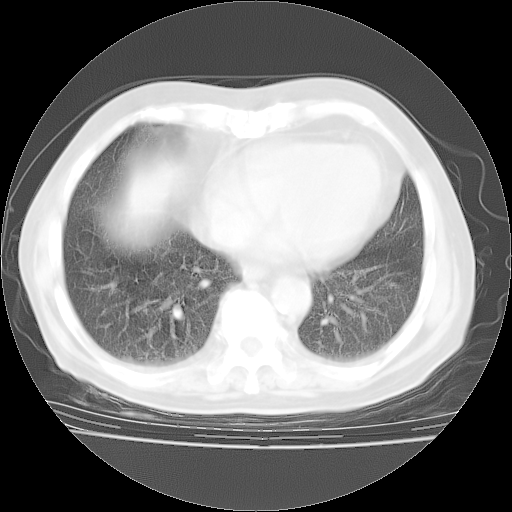

今天部分检查

轻微咳嗽,无痰,(体温正常时)R20次/分,P75次/分,双肺底、腋下可闻及少量捻发音。下肢轻度浮肿。

血常规:白细胞9.11×109/L,N0.92,L5.64,血小板39.2×109/L,HB148g/L,ESR2mm/H。

尿常规:潜血+

血生化:总蛋白69.71g/L,白蛋白38.40g/L,球蛋白31.31g/L,CRP27.9mg/L,尿素氮11.98mmol/L,肌酐106μmol/L,乳酸脱氢酶1099 U/L,肌酸激酶108U/L,CK-MB 61U/L。

腹部B超:胆囊壁增厚,肝、胆、胰、脾、肾无异常,肠系膜淋巴结、腹膜后淋巴结无增大。

ECG:右心室增大

心脏超声检查:无右心室增大。

增加治疗:异烟肼、利福平、乙胺丁醇,静滴左氧氟沙星、参麦注射液。甲强龙从80mg暂减为40mg。

强的松3月1日改为10mg qd,4月1日改为10mg qod。3月份以前的减量过程和环磷酰胺疗程需等明天查看记录(我岳父自己做的记录在他家里)。